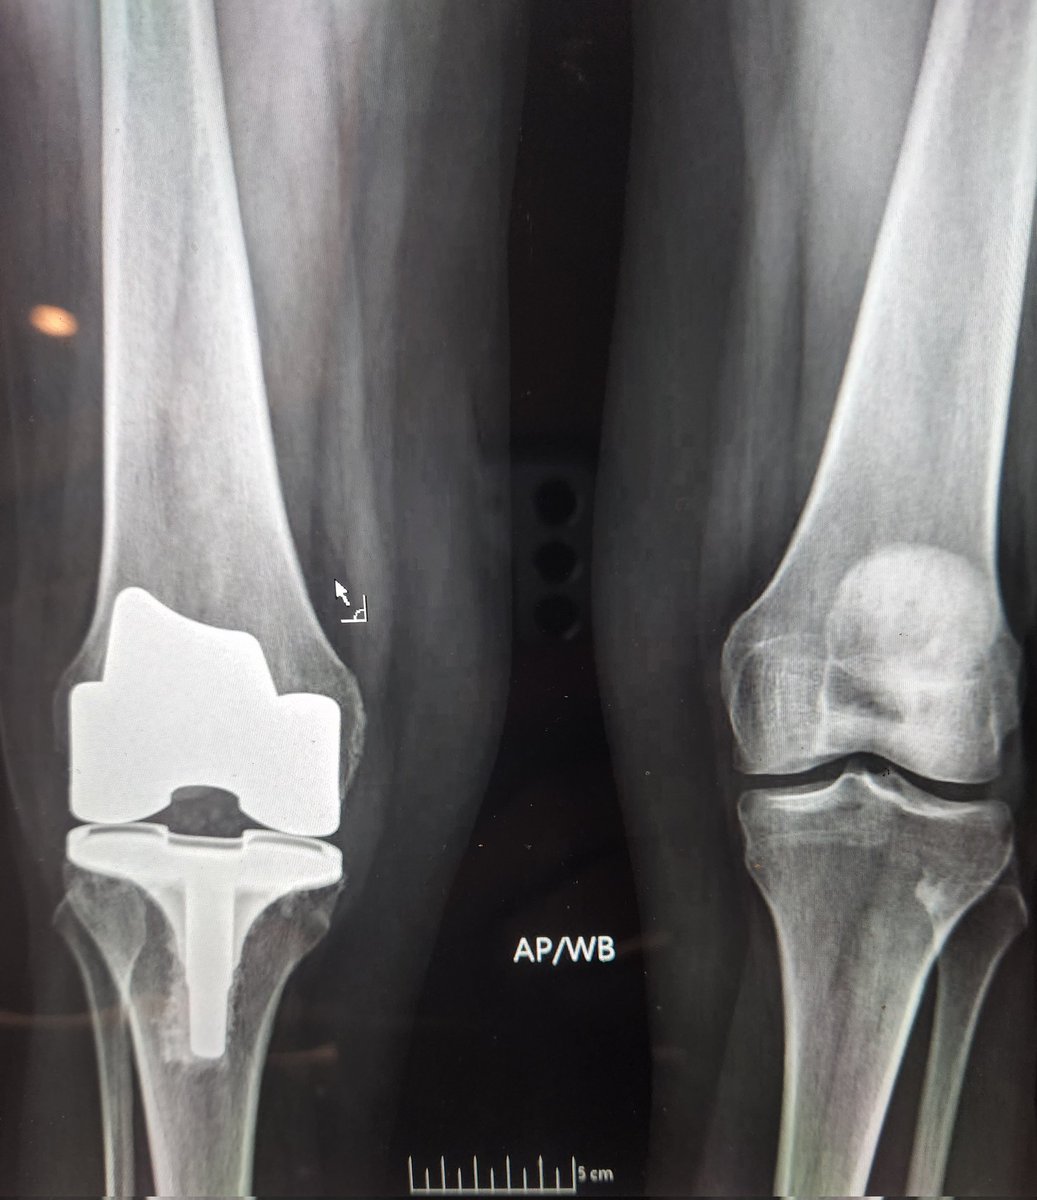

@CenterRotation @djschuett @kate_wynne @Dr_Stambough @BrianChalmersMD @jaimelbellamyDO @ashtongoldmanmd @EdinburghKnee @generalorthomd @orthosmash69 @txsportsdoc I mean I thought part of the joint surgeon uniform was total knee socks 🤷🏼♂️ Am I doing it wrong?